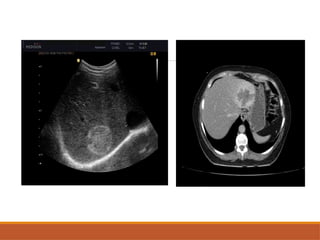

Metastases

Liver is the most common site of metastasis.

Usually multiple.

Majorities are hypovascular (GI tract,lung breast& head,neck

tumour, lymphoma).

Hypervascular metastasis are less .(NET, RCC, carcinoid, sarcoma,

melanoma).

USG

•rounded and well-defined

•positive mass effect with distortion of adjacent vessels

•hypoechoic: most common ~65% and is a concerning

feature

•hypoechoic halo due to compressed and fat-spared liver

•cystic, calcified, infiltrative, and echogenic appearances

are all possible

CT SCAN

NECT: Typically hypodense, may be iso or

hyperdense, cystic, mixed,calcified.

CECT: Enhancement is typically peripheral in

arterial phase & washout in delayed phase.

• #54 Grey scale usg image sshowing multiple well dined isoecheic lesions noted with peripheral hypoecheic rim with internal vasculairity Another rimage sshowing multiple hyperecheic leisons

• #56 Axial cect image showing well defined peripherally ehnacing lesion with washout of contart in delayed phases